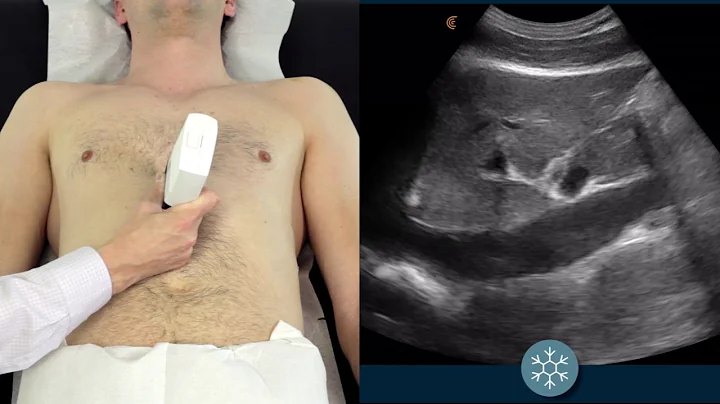

Ivc Ultrasound Step By Step - Easiest Method

Step by Step instructions on Performing IVC Ultrasound in the Easiest way Possible!